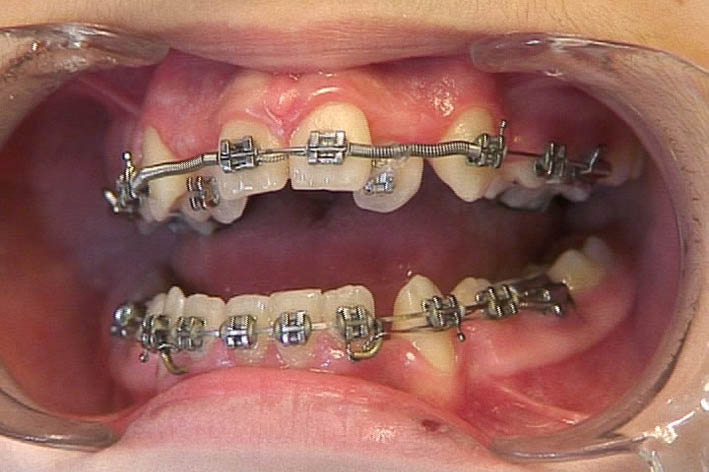

اگر استریپ قدامی کردهاید و فضا بین قدامیها ایجاد شده یا بین دندانهای قدامی Space وجود دارد میتوانید چینالاستیک را از براکت کانین تا کانین به مدت یک ماه بگذارید (شکل 156-1) اگر فضا بسته نشد هر ماه Chain Elastic را عوض میکنید تا سرانجام فضا بسته شود. بعد از بسته شدن فضا آن را برمیداریم و به صورت ضربدری از کانین تا کانین با سیم لیگاچور figure ∞ میزنیم تا فضا مجدداً باز نشود. بعد از اینکه فضا را بستیم اگر باز هم چینالاستیک بماند ایجاد کرادینگ میکند.

ضمناً حتماً باید کانینهای دو طرف با سیم لیگاچور بسته شود تا از چرخش آنها جلوگیری گردد. آرچوایر هم 0.020 استیل باشد تا جلوی tilt دیستالی یا مزیالی دندانها گرفته شود.

شکل 156-1: بستن فضاهای قدامی به کمک چین الاستیک